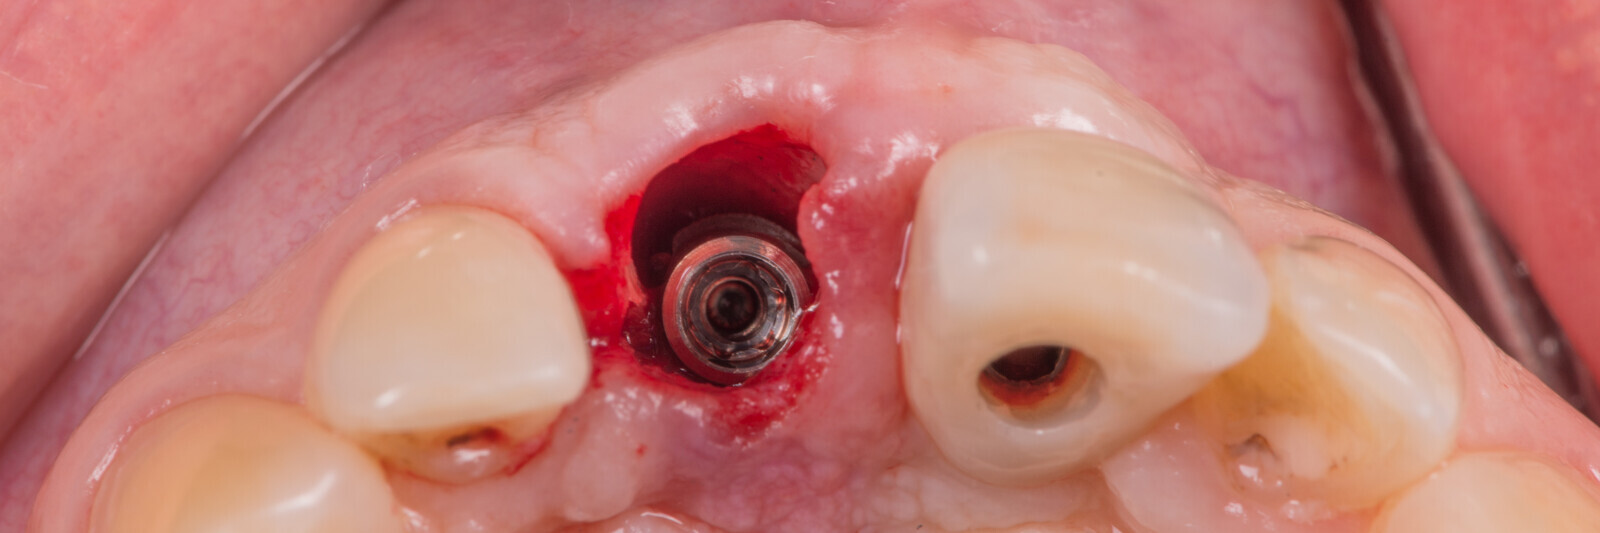

Immediate placement and restoration of a Straumann BLX implant replacing maxillary incisors